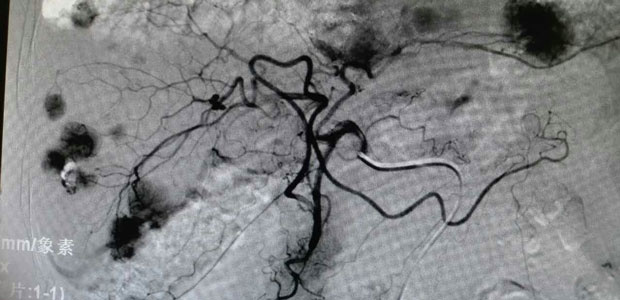

During the operation, the doctor firstly conducted femoral artery puncture with local anaesthesia to patient., channeling the front end of catheter into celiac artery, proper hepatic artery and arteries on both left and right liver to detect the tumor lesion.

Secondly, the doctor identified each supplying artery by catheter and performed drug injection and embolism.